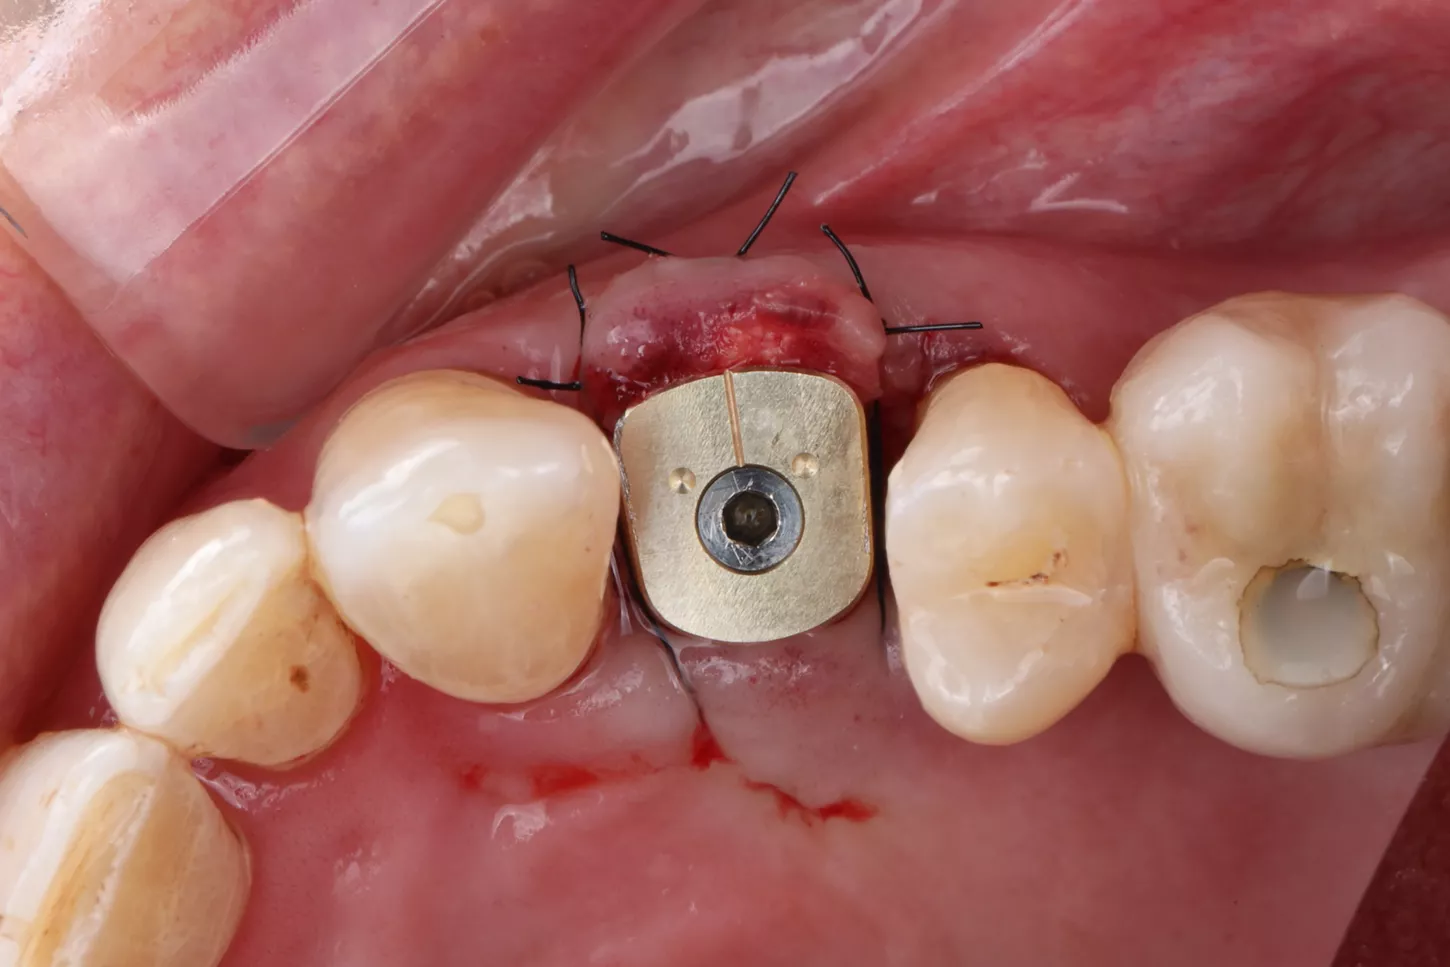

Phase III: Guide design (Fig 3a. 3b. 3c) for guided Implant Placement and Soft-Tissue Augmentation

After healing, implant placement was performed using a tooth-supported surgical guide under local anaesthesia. A limited buccal flap allowed visual control and creation of a pouch for a connective tissue graft. Osteotomy was completed with the Integral surgery kit, and a 3.4×12 mm Axiom® X3 implant (XT34120) was placed under fully guided conditions with a Healfit® SH (OPSHSC23) healing abutment connected. A palatal connective tissue graft was positioned buccally to enhance soft-tissue thickness. The flap was sutured with 5-0 interrupted and mattress sutures. Postoperative care mirrored Phase I, with uneventful healing observed (Fig 4 a&b).

4a. 4b. Lateral view showing Healfit® SH healing screw connected to the implant and occlusal view of sutures for tension-free closure.